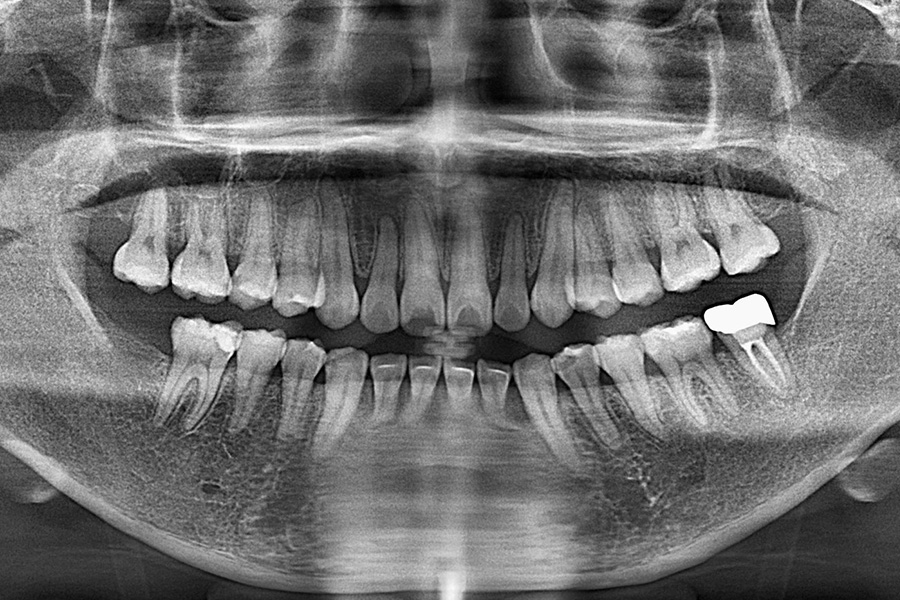

治療後(CT)

治療内容 右下7のインプラント治療(1本)

治療に伴うリスク 手術中に神経に触れることがあり、麻痺や痺れ、痛みが生じることがあります。骨が弱い場合、インプラントが安定せずに外れることがあります。